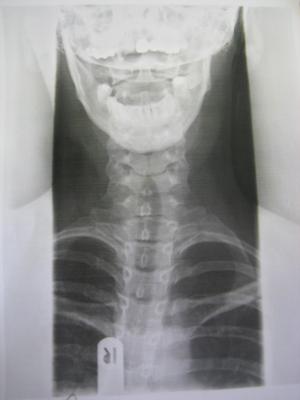

Heute war ich hier beim Durchgangsarzt,da momentan alle Orthopäden hier Urlaub haben bis nach Ostern und ich Probleme habe meinen Kopf vernünftig zu bewegen.Er hat Röntgenbilder gemacht und ich hab einen richtigen Schock bekommen.Das was ich vermutet habe,hat sich wohl bestätigt,es ist schlimmer geworden mit der Skoliose und ich muss sofort zu einem Orthopäden.Ich habe stärkere Schmerzmittel bekommen und mein Arzt meint,ich brauche wohl ein Korsett.....

Ich hab mal die Bilder vom Röntgen angehängt.Den Grad der Verkrümmung weiss ich leider noch nicht.Aber kann mir vielleicht jemand was zu den Bildern sagen?

forum_photo1.jpg

forum_photo1.jpg (9.02 KiB) 4237 mal betrachtet

hat schon mal jemand deinen Kiefer untersucht, ob der gerade ist? Sieht auf dem einen Bild nicht so aus, allerdings habe ich von Röntgenbildern absolut keine Ahnung! Nur so viel: Meine Arbeitskollegin mußte nach ihrer Schwangerschaft auch ihren Kiefer sanieren, weil er sich verändert hatte. Und aus eigener Erfahrung kann ich nur sagen, das ein schiefer Kiefer sich auf den ganzen Körper auswirkt! Und leider hat das über 30 Jahre die verschiedensten Ärzte nicht festgestellt :<

Für das Röntgenbild musste ich den Mund ganz weit aufmachen,ich sehe aber auch auf den Bildern das es schief aussieht.Werde das auf jeden Fall beim Orthopäden auch mal ansprechen.

Ja, Kiefer sieht wirklich schief aus.

Der Rücken sieht doch, was man auf den Bildern erkennen kann, gar net so schlimm aus.

Allerdings sieht man halt vom unteren Rücken nichts.